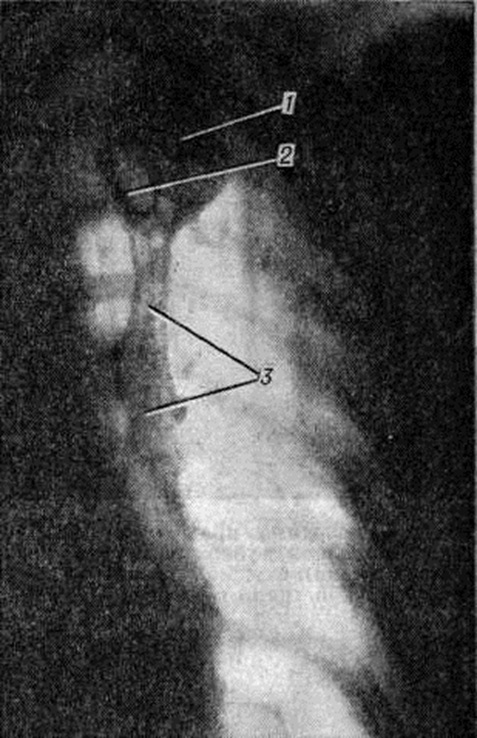

Рис. 1.

Гистотопограмма лёгкого при первичном туберкулёзном комплексе: 1 — очаг казеозного некроза в лёгочной ткани в стадии начавшегося отграничения; 2 — казеозный некроз лимфатических узлов в области корня лёгкого; 3 — воспалительные изменения лимфатических сосудов, соединяющих очаг в лёгком с лимфатическими узлами корня лёгкого — туберкулёзный лимфангиит.